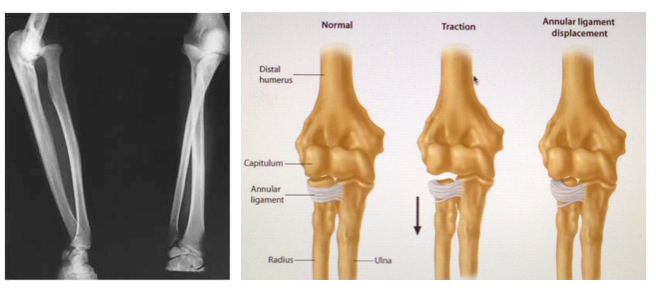

What is radial head subluxation?